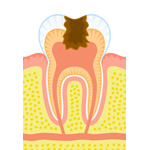

●C0(ごく初期の虫歯)

●C0(ごく初期の虫歯)

まだ穴は開いていませんが、表面が溶け始めた状態です。ブラッシング指導、フッ素塗布などで再石灰化を促し、自然治癒させることができます。

●C1(歯の表面の虫歯)

●C1(歯の表面の虫歯)

歯の表面のエナメル質にだけ穴が開いた状態です。この段階では痛みなどの自覚症状はありませんが、放置すると進行してしまいます。虫歯の部分を削り、詰め物をする治療が必要です。または、予防をすることにより無駄に歯を削らずに虫歯の進行を遅らせます。

●C2(神経に近い虫歯)

●C2(神経に近い虫歯)

エナメル質の内側にある象牙質まで進んだ状態です。神経には達していませんが、冷たい水や甘いものが歯にしみることもあります。虫歯の部分を削り取り、詰め物をする治療が必要です。

●C3(神経にまで達した虫歯)

●C3(神経にまで達した虫歯)

神経がとおっている歯髄の部分にまで達した状態です。この段階になると、歯の根の部分に炎症が起きていることもあります。麻酔をして歯を大きく削り取り、詰め物か被せ物をします。

●C4(末期の虫歯)

●C4(末期の虫歯)

歯の頭の部分が腐ってしまい、歯の根しか残っていない状態です。通常は抜歯するしかありません。